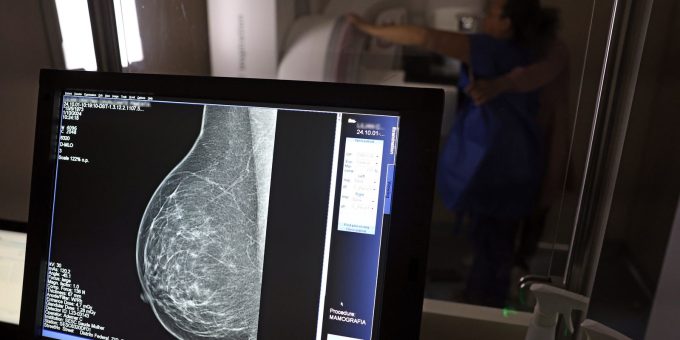

mamografia

Vigitel: 92% das brasileiras entre 50 e 69 anos fizeram mamografia

A pesquisa do Sistema de Vigilância de Fatores de Risco e Proteção para Doenças Crônicas por Inquérito Telefônico (Vigitel) do Ministério da Saúde...

5 de fevereiro de 2026Lei garante mamografia pelo SUS para mulheres a partir dos 40 anos

Utilizado para o diagnóstico precoce de câncer de mama, o exame de mamografia gratuito no Sistema Único de Saúde (SUS) agora é um...

23 de outubro de 2025Inca estima 73,6 mil novos casos de câncer de mama no Brasil em 2025

3 de outubro de 2025Ministério da Saúde passa a recomendar mamografia a partir dos 40 anos

O Ministério da Saúde passou a recomendar o acesso a mamografia, via Sistema Único de Saúde (SUS), para mulheres de 40 a 49...